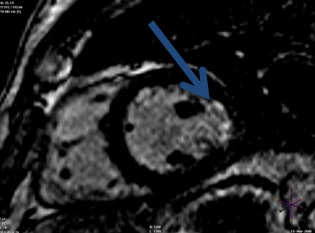

Late gadolinium enhancement image shows a small subendocardial lateral myocardial infarction (blue arrow).

Late gadolinium enhancement image shows a small subendocardial lateral myocardial infarction (blue arrow).For cardiac MR perfusion exams, the necessity to induce hyperemic stress in patients can be achieved by administering adenosine for four minutes (or dobutamine if adenosine is contraindicated) followed by rest. The difference between late gadolinium enhancement and perfusion exams is that radiologists watch whilst the gadolinium washes in, he said. Patients must avoid caffeine for six hours prior to the procedure. Because of the likelihood of patients requiring serial images over time during their disease process, it is essential to be consistent in procedural techniques, especially when performing perfusion exams; making a comparative analysis from previous scans to more recent ones can be made more difficult if varying techniques are used.